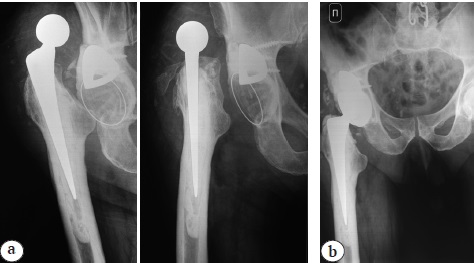

In July 2016, total hybrid arthroplasty was performed in the local hospital for idiopathic right-sided hip osteoarthritis. The postoperative period was uneventful. In September 2017, the patient fell on his right side and was admitted to the hospital again. No signs of skeletal trauma were found, and he was discharged with the diagnosis of "soft tissue bruise of the right thigh". Pain syndrome was persisting, and some time later hyperemia and swelling appeared. In October 2019, the patient was consulted by a surgeon of the septic surgery department on an outpatient basis: diagnostic joint puncture was performed, S. maltophilia strain was isolated from the aspirate. Surgical treatment for the diagnosed chronic PPI was recommended. Diagnosis on admission: orthopedic joint implants, total arthroplasty of the right hip (2016), chronic deep surgical site infection (CDSSI), chronic osteomyelitis of the right femur and pelvis 3B (l). On admission, X-ray exa-mination showed instability of the cementless acetabular component of the right hip prosthesis with dislocation of the femoral head. Cemented femoral component was stable (Fig. 1 a). Lab tests revealed signs of an exacerbation of the infection: WBC – 8.3×109/l, erythrocyte sedimentation rate – 57 mm/min, CRP – 143 mg/l, and a decrease in the filtration capacity of the kidneys: blood creatinine – 118 μmol/l, estimated creatinine clearance (CC) – 71.6 ml/min.

Control X-ray the first day after the surgery showed the replacement of the right hip with a total prosthesis with cemented fixation of the components in the correct stable position. Postoperative period was uneventful (Fig. 1b). The drains were removed on the 5th day. The wound healed with primary intension. S. maltophilia strain was isolated from all intraoperatively sampled materials, which did not require ABT correction. The sutures were removed on the 14th day. The patient was discharged in satisfactory condition with the re-commendation to take co-trimoxazole tablets 0.96 g 2 times a day for 8 weeks and to monitor the clinical blood count, creatinine, transaminases once every 2 weeks to detect possible adverse reactions.

Fig. 1. X-rays of the right hip: a — on admission with signs of acetabular component instability and prosthetic head dislocation; b — after one-stage revision arthroplasty